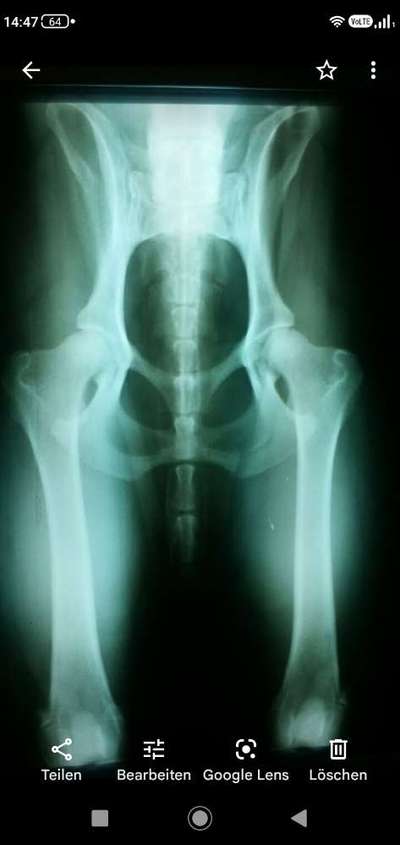

Der Hund (Griffon Korthals) von meiner Freundin hat angefangen zu lahmen. TK diagnostizierte ohne röntgen HD. Meine Freundin wollte eine 2te Meinung. Bei dem TA ist dann auch ein Röntgenbild gemacht worden. Dabei stellte sich heraus dass der Hund keine HD hat sondern eine alte Fraktur die nicht richtig verheilt ist. Kann mir jemand mit Hilfe des röntgen Bild sagen ob da eine Fraktur zu sehen ist. Im voraus schon einmal Danke. Liebe Grüße Anette

Ein abfotografiertes Röntgenbild ist aufgrund möglicher Spiegelungen, der Unschärfe, „verfälschter“ Belichtung und Optik leider nicht auswertbar. Darüberhinaus sollte die betroffene Struktur zur Beurteilung immer mindestens in zwei Ebenen erfolgen, da es durch Überlagerungen zu Fehldiagnosen kommen kann.

Zur Diagnose einer HD müssen entsprechende Winkelmessungen der Hüftgelenke am Röntgenbild erfolgen.

Je nach Art der Fraktur kann beispielsweise eine sogenannte Kallusbildung im Bereich der Fraktur sichtbar sein. Hierbei handelt es sich um narbenartige Zubildungen des Knochens, welche im späteren Verlauf durch Calciumeinlagerungen röntgenologisch zu sehen sind. Bei unbehandelten Knochenbrüchen kann es zu Arthrosen kommen.